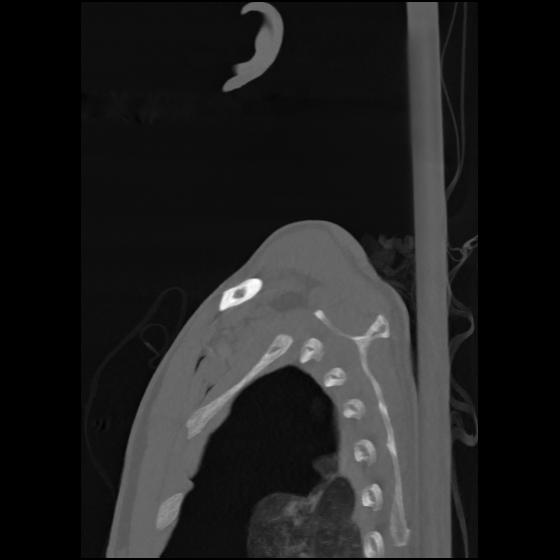

24 ANGIO,CE,Sag-MIP,5.000,ANGIO,Sag-MIP,